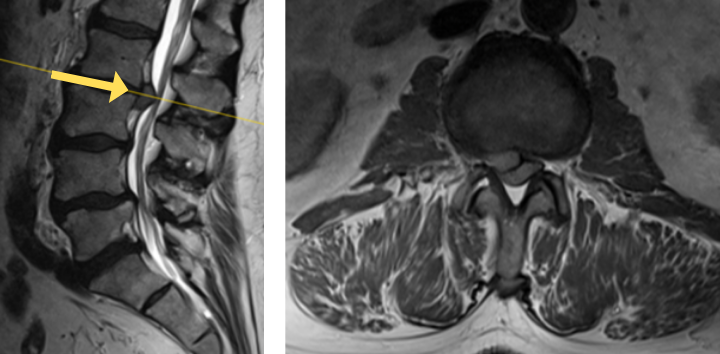

His MRI lumbar spine showed a herniated disc at L2/L3 and a grade 1 spondylolisthesis at L4/L5. Both of these findings were contributing to the patients back and leg pain.

Image 1A shows central stenosis at L4/L5 level associated with grade 1 spondylolisthesis.

Image 1B shows disc herniation at L2/L3.